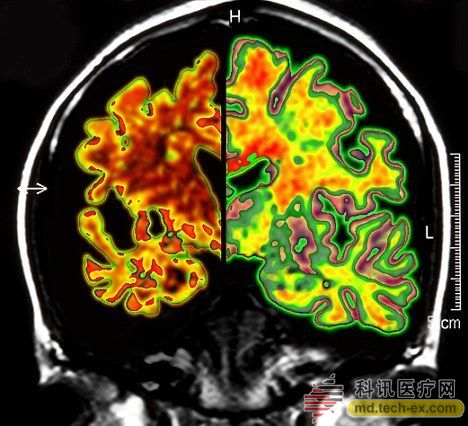

在手術(shù)中,所有病患的腦部將被植入電極,這些電極與一個(gè)類似起搏器的裝置相連接,能夠每秒鐘發(fā)出130次電脈沖。羅森博格表示,病人并不會(huì)感受到電脈沖的存在。 研究人員表示,所有接受臨床試驗(yàn)的病人同時(shí)都會(huì)被植入這個(gè)“起搏器”裝置。其中,一半病人的“起搏器”將于手術(shù)后兩周開(kāi)啟,而另一半病人的要在手術(shù)后一年才會(huì)開(kāi)啟。目前,參加臨床試驗(yàn)的病人和醫(yī)生并不知道分組情況。 其實(shí)早在2010年,加拿大就已經(jīng)對(duì)這種大腦“起搏器”展開(kāi)臨床試驗(yàn)。當(dāng)時(shí),有6名輕微老年癡呆癥患者參加。當(dāng)時(shí)的試驗(yàn)結(jié)果顯示,在13個(gè)月的觀察期中,這些病患的葡糖糖代謝速度持續(xù)上升,這也就說(shuō)明他們的大腦神經(jīng)元正在工作。而在同時(shí)期內(nèi),大部分老年癡呆癥患者的葡萄糖代謝水平則是在不斷下降。